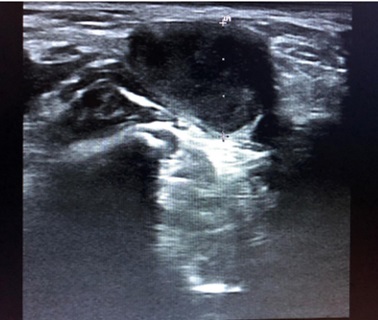

Niño de 7 años que tras vacunación de SARS-CoV-2 presenta bultoma axilar derecho generando asimetría a nivel pectoral. Asintomático. En la exploración física: adenopatía de consistencia elástica, móvil y dolorosa a la palpación. Se realiza ecografía objetivando una adenopatía hipoecoica, ovalada de 15 mm de diámetro anteroposterior, bordes hiperecogénicos bien delimitados e hilio llamativamente grande (Fig. 1) con vascularización central (Fig. 2). Diagnóstico de adenopatía reactiva, con seguimiento ecográfico al mes (Fig. 3) y disminución del tamaño.

Figura 1. Adenopatía hipoecoica con hilio grande

Figura 1. Adenopatía hipoecoica.